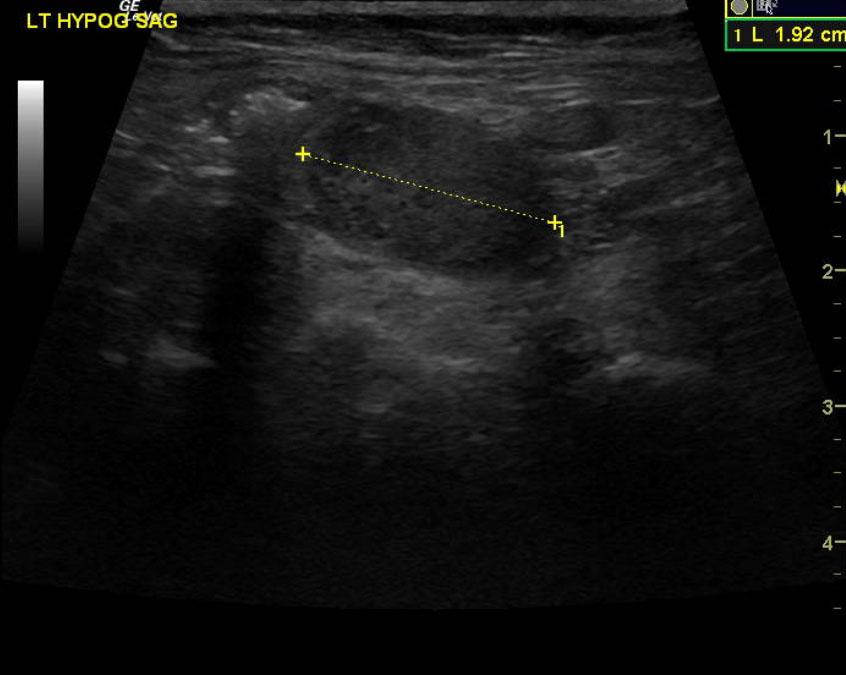

Mineralizing prostatic mass extending into the preprostatic urethra and trigone with local iliac lymphadenopathy. These images are strongly suggestive for metastatic prostatic carcinoma.

The prostate presented multi focal mineralization with swollen contour with minor polypoid changes and hyperechoic surrounding fat. This projected into the trigone. The mineralizing, prostatic mass measured 2.9 cm and infiltrated into the preprostatic urethra and likely post prostatic urethra. Iliac lymphadenopathy was noted.